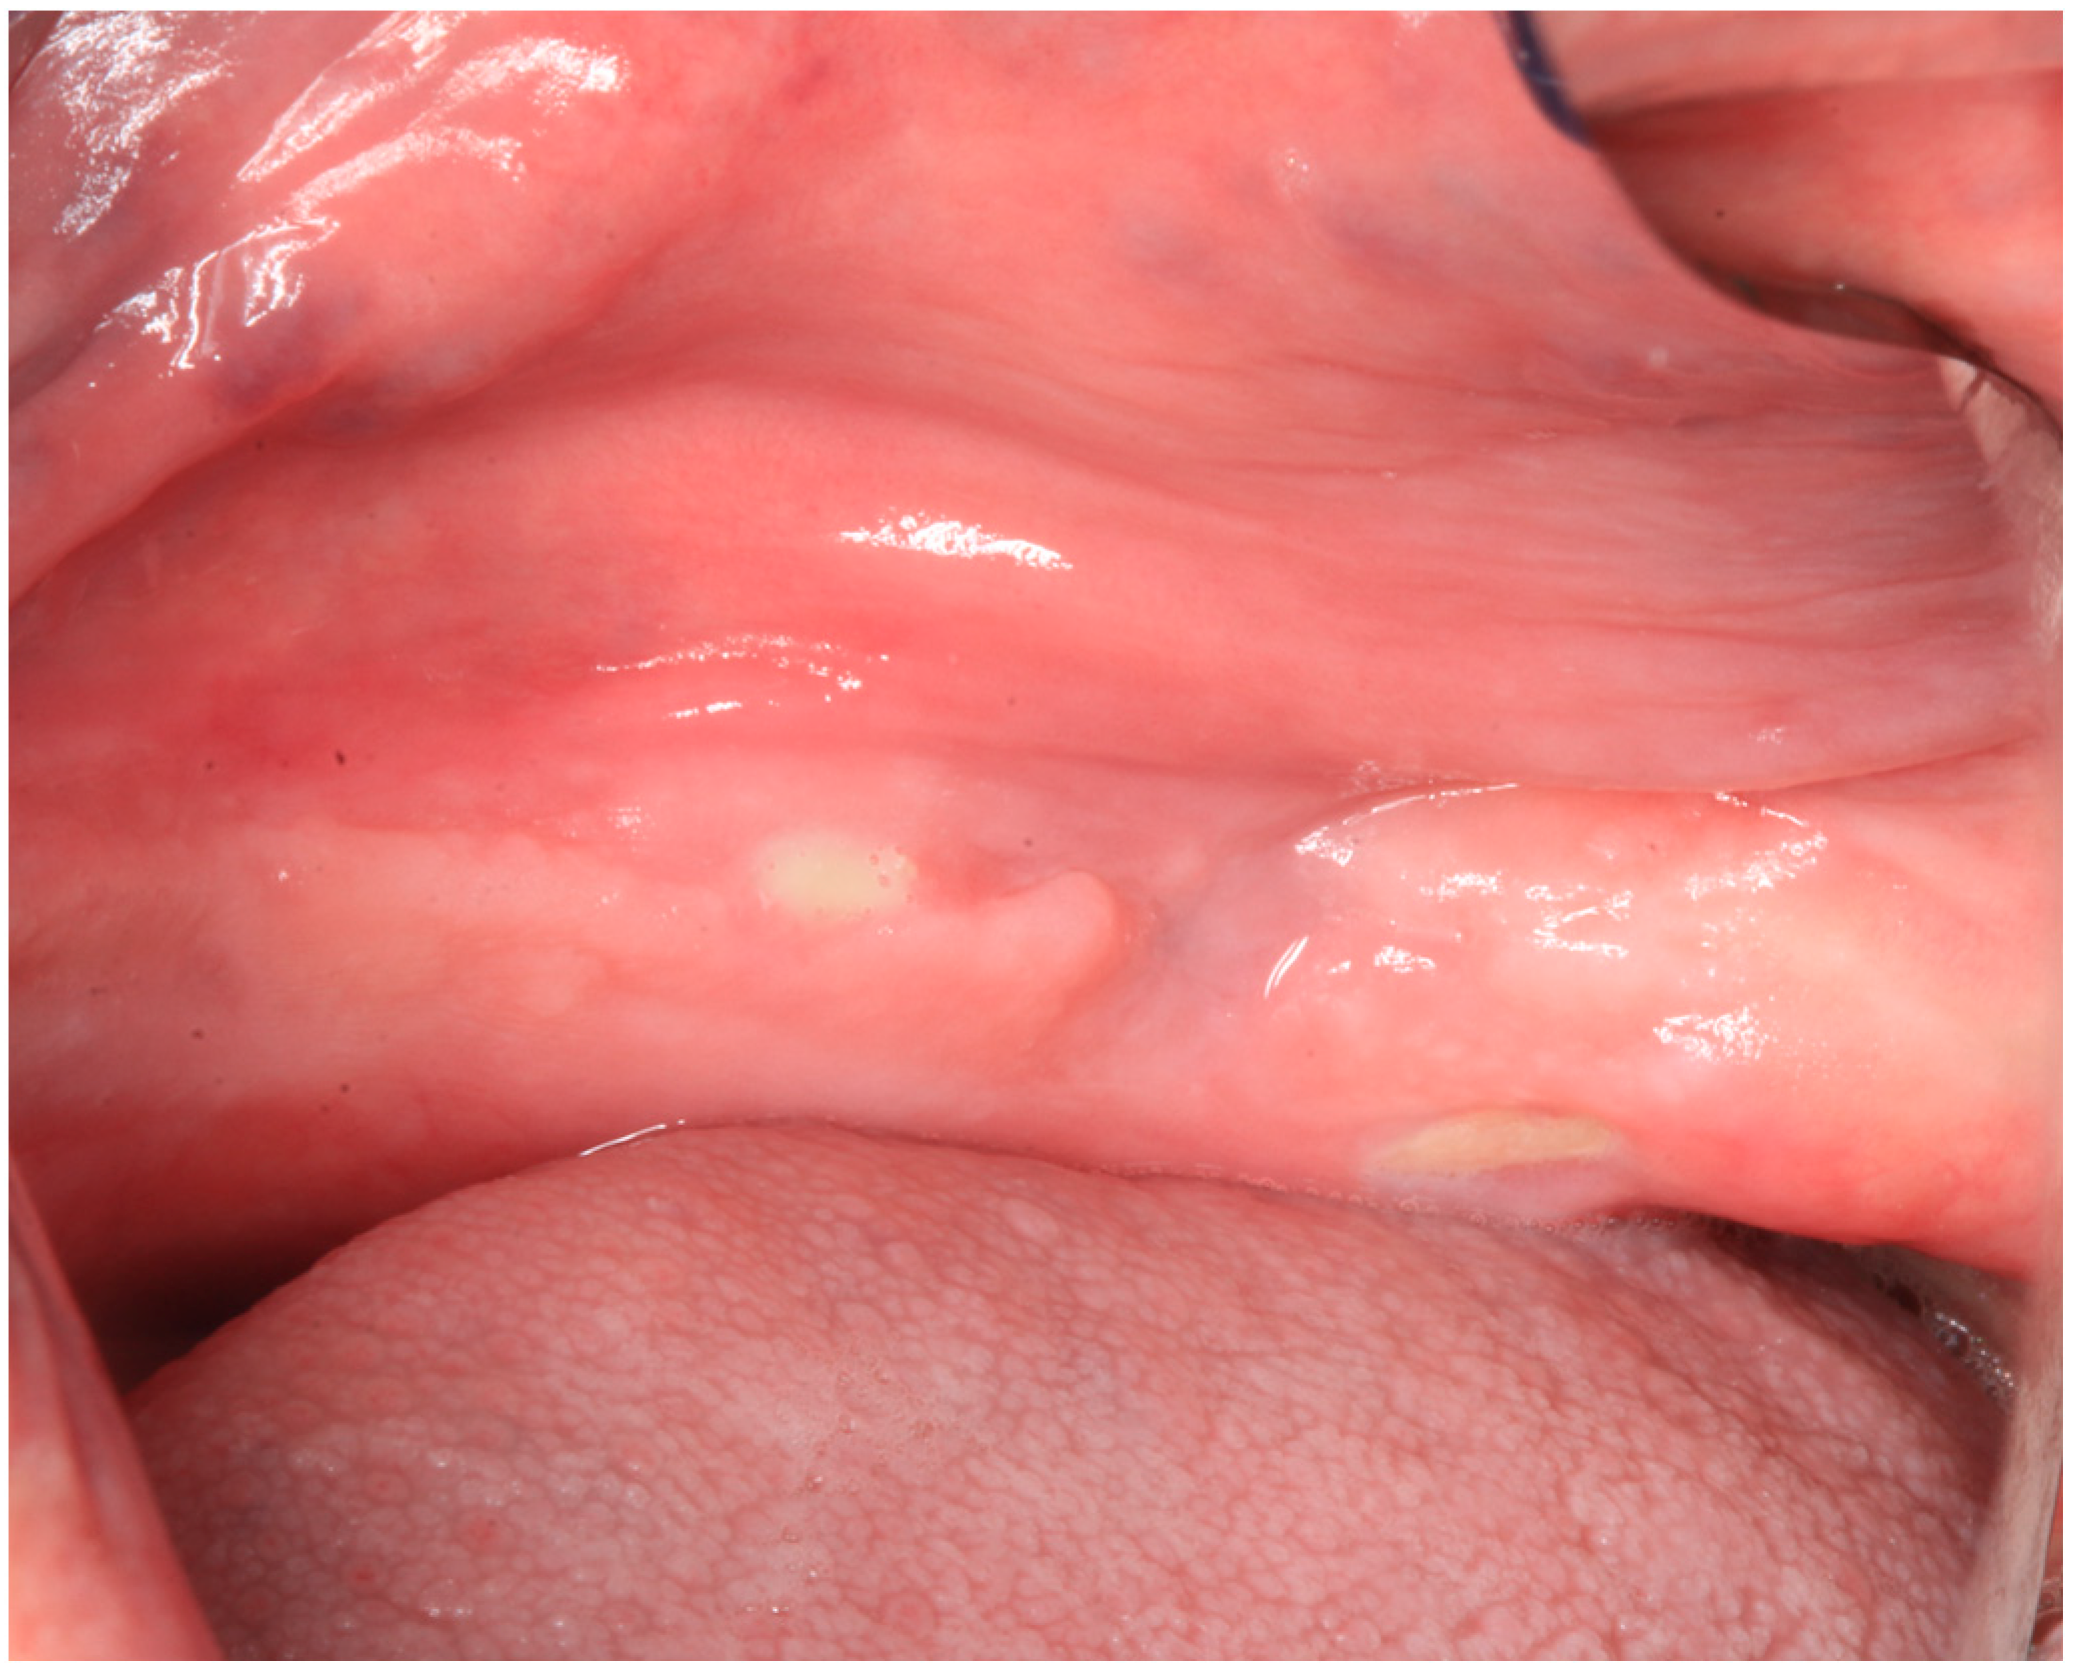

2.1. Case Report 1

2.2. Case Report 2